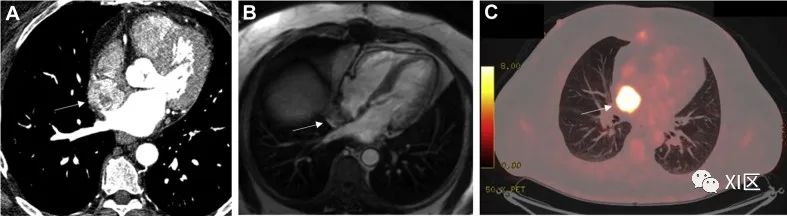

脂肪瘤(图 3)是第二大最常见的原发性心脏良性肿瘤(8% 至 12%),最常见于中老年人。大约 50%的脂肪瘤起源于心内膜下层,另一半起源于心外膜下层或心肌层并长入心包囊。它们通常没有症状,但可能会导致心律失常或瓣膜功能障碍。心外膜下脂肪瘤可压迫冠状动脉,导致缺血性胸痛。

图 3 脂肪瘤65 岁男性,偶然发现心脏肿块。(A)经胸超声心动图长轴切面上的卵圆形肿块(白色箭头)。(B)CMR 稳态自由进动(SSFP)序列显示,左心室基底前隐窝处的包块(白色箭头)呈环状,未造成任何左心室流出道梗阻。(C)CMR 脂肪-水抑制成像显示肿块(白色箭头)信号完全被抑制。

在 TTE 上,脂肪瘤多为宽基底、不活动、无蒂、边界清楚的肿块。脂肪瘤呈均质性,无钙化迹象,在腔内呈高回声,但在心包内呈低回声。心脏 CT 可显示位于心腔、心肌或心包内的脂肪衰减均匀、不增强的肿块。在 CMR 的 T1 加权成像上,脂肪瘤相对于心肌具有特征性的均匀高信号强度,在应用额外的脂肪饱和预脉冲时,这种信号强度会被明显抑制。在 T2 成像中,脂肪瘤呈高信号;在脂肪饱和成像中,脂肪瘤呈明显的低信号。使用造影剂后,脂肪瘤不会出现灌注。除症状严重的病例外,一般不需要手术切除。